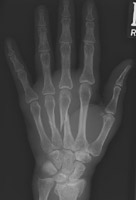

- Click on the image for a larger versionAPA radiograph of the hand. This demonstrates a comminuted fracture of the base of the fifth metacarpal.